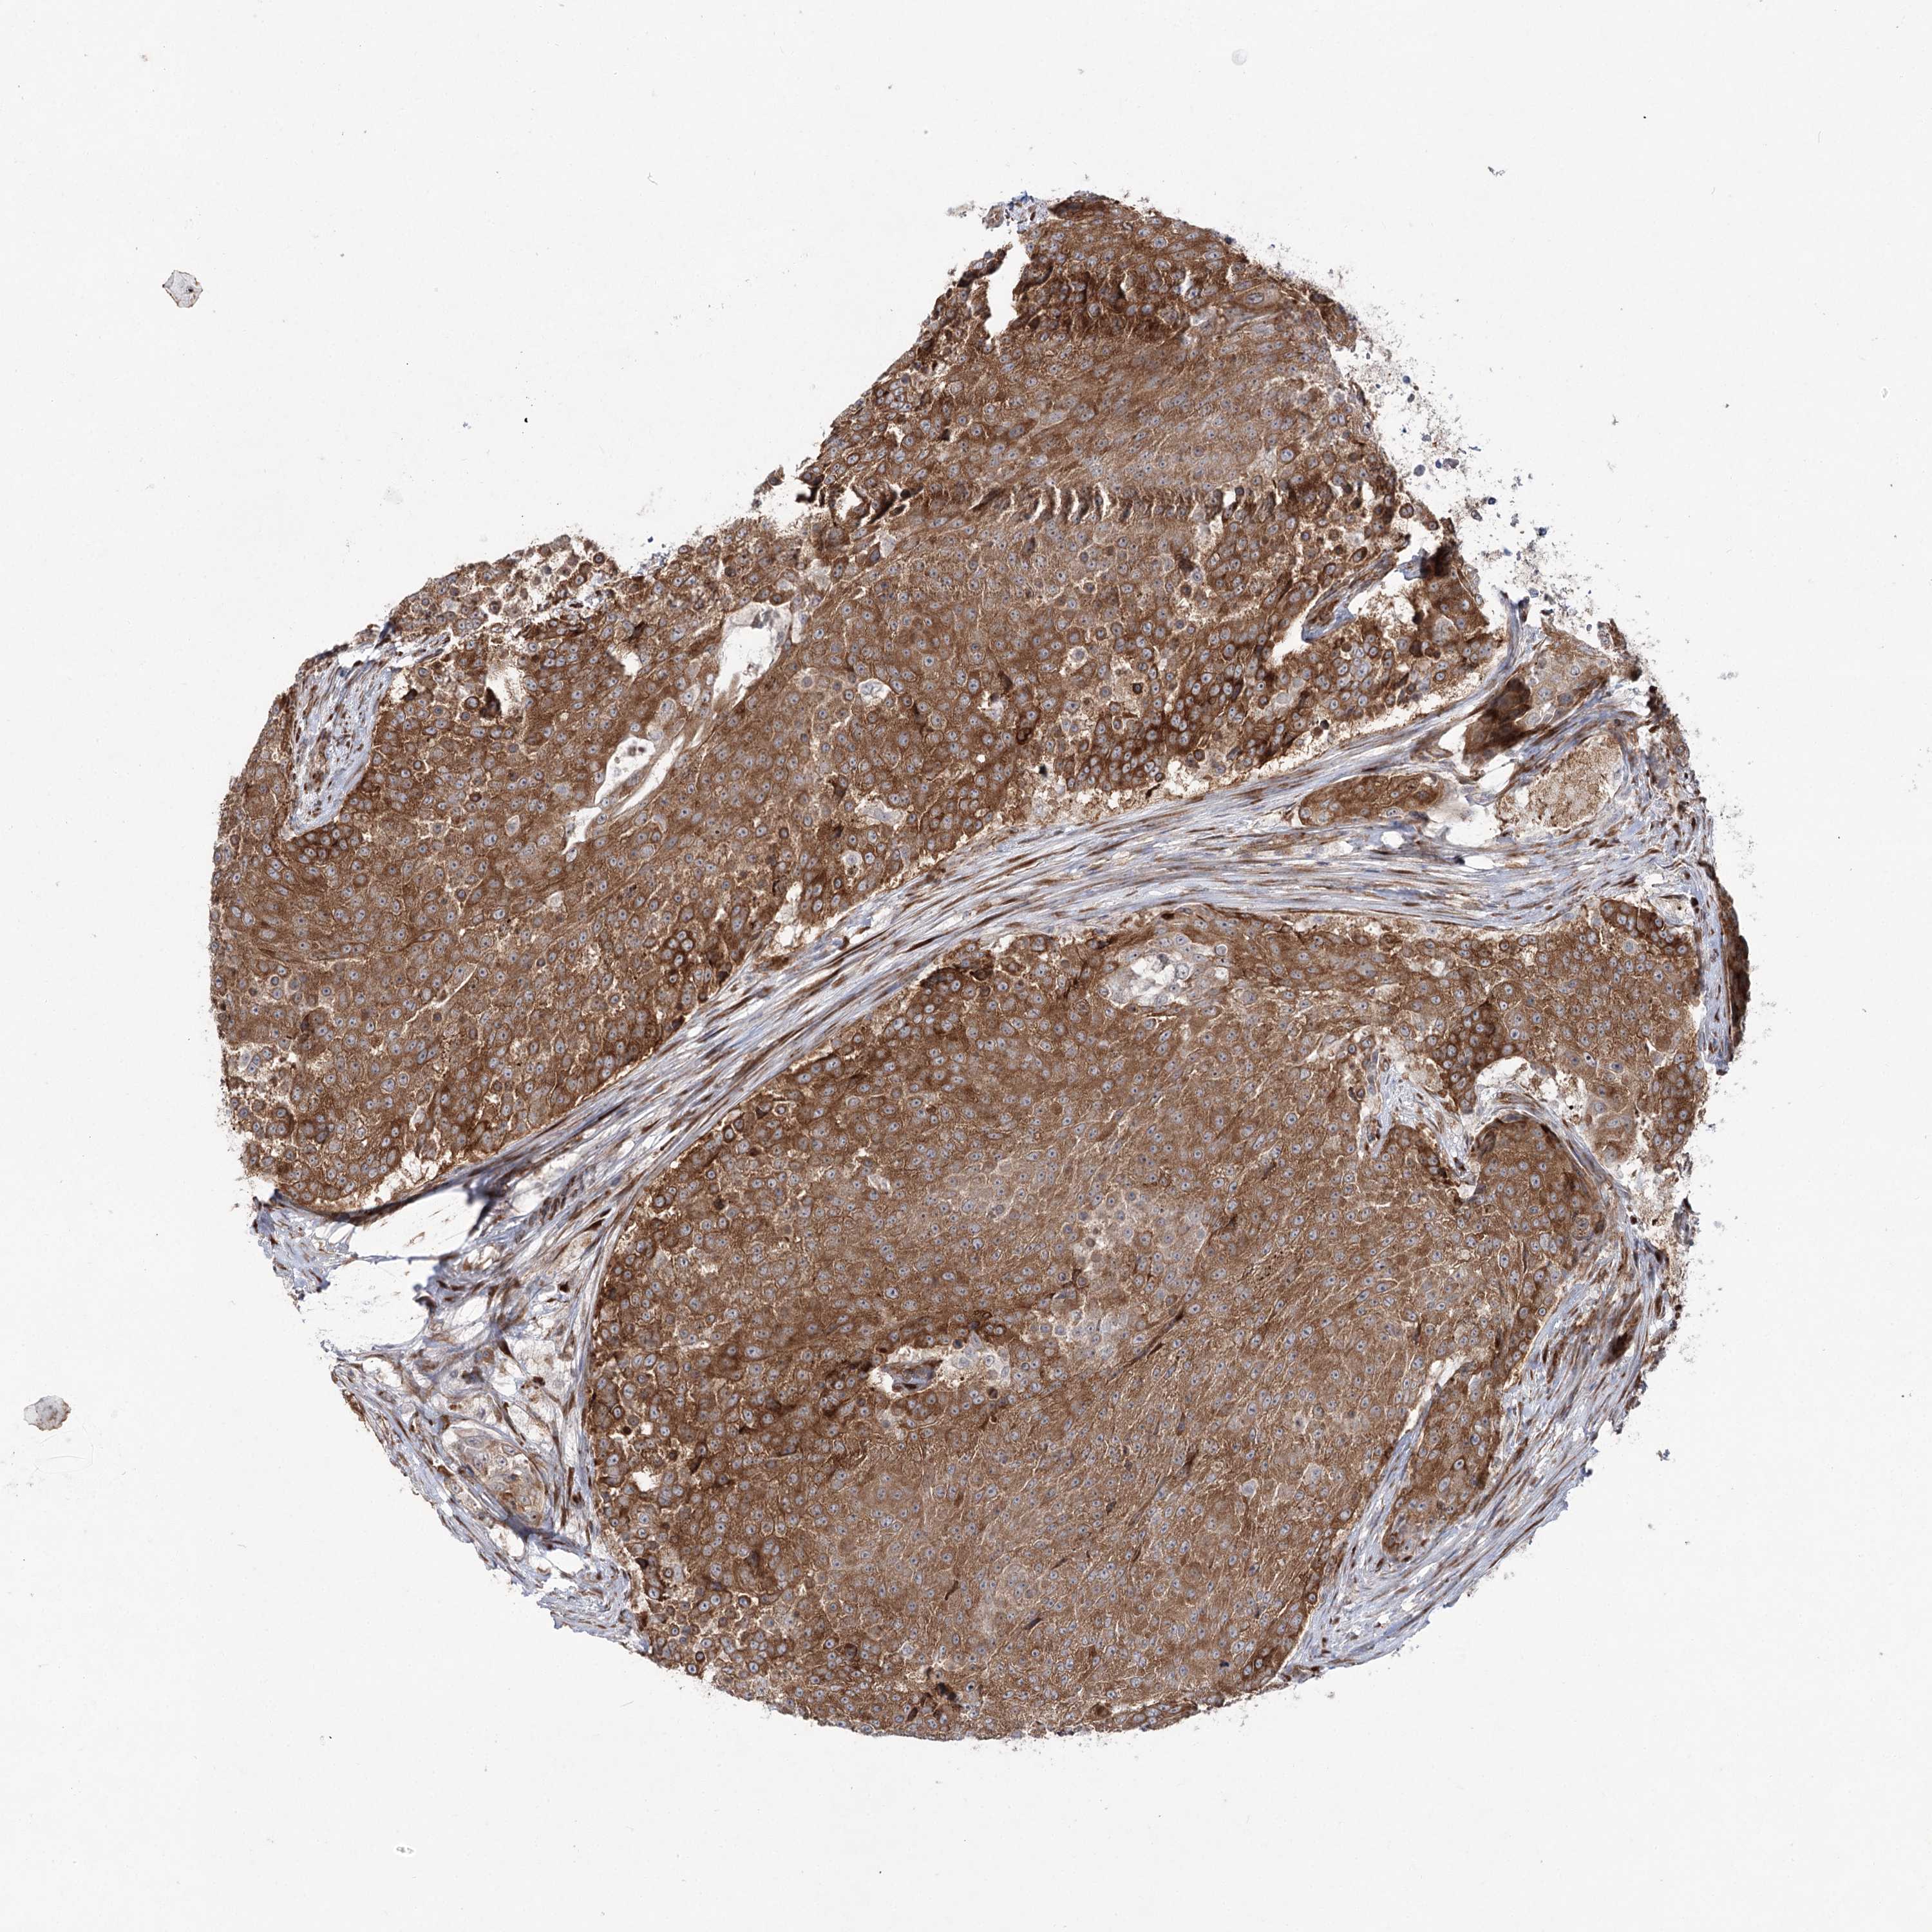

UROTHELIAL CANCER - Protein expressioni

A mouse-over function shows sample information and annotation data. Click on an image to view it in a full screen mode. Samples can be filtered based on level of antibody staining by selecting one or several of the following categories: high, medium, low and not detected. The assay and annotation is described here.

Note that samples used for immunohistochemistry by the Human Protein Atlas do not correspond to samples in the TCGA dataset.

Antibody stainingi

Antibody staining in the annotated cell types in the current human tissue is reported as not detected, low, medium, or high, based on conventional immunohistochemistry profiling in selected tissues. This score is based on the combination of the staining intensity and fraction of stained cells.

Each image is clickable and will lead to virtual microscopy that enables deeper exploration of all samples and also displays staining intensity scores, fraction scores and subcellular localization as well as patient and tissue information for each sample.

Antibody HPA037847

Staining

High

Medium

Low

Not detected

Intensity

Strong

Moderate

Weak

Negative

Quantity

>75%

75%-25%

<25%

None

Location

Nuclear

Cytoplasmic/membranous

Cytoplasmic/membranous,nuclear

Urothelial carcinoma, High grade

Urothelial carcinoma, Low grade

Urothelial carcinoma, NOS